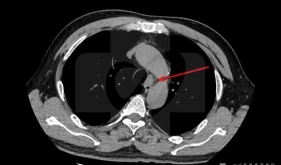

• 什么是肺部小钙化灶

• 肺上长结节是不是就“癌”起了?

• 肺癌的手术治疗